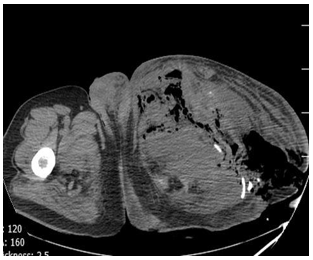

Abdominal ultrasound did not show hepatic or other visceral involvement. Pelvic ultrasound indicated a collection include necrotic tissues, gas bubbles, and discharge in the left side of pelvic cavity. Chest x-ray (CXR) was normal. A computed tomography scan showed destruction lesions in the left hemi pelvis, sacrum, and the left proximal femur, as well (Figures 2-5).

Figure 4: CT-scan of pelvic show distraction of iliac, scum bone, hipe joint and distracion of femur neck.

Figure 5: CT-scan of pelvic show distraction ofhipe joint and proximal portion of femure with sever swelling and air in the muscles.